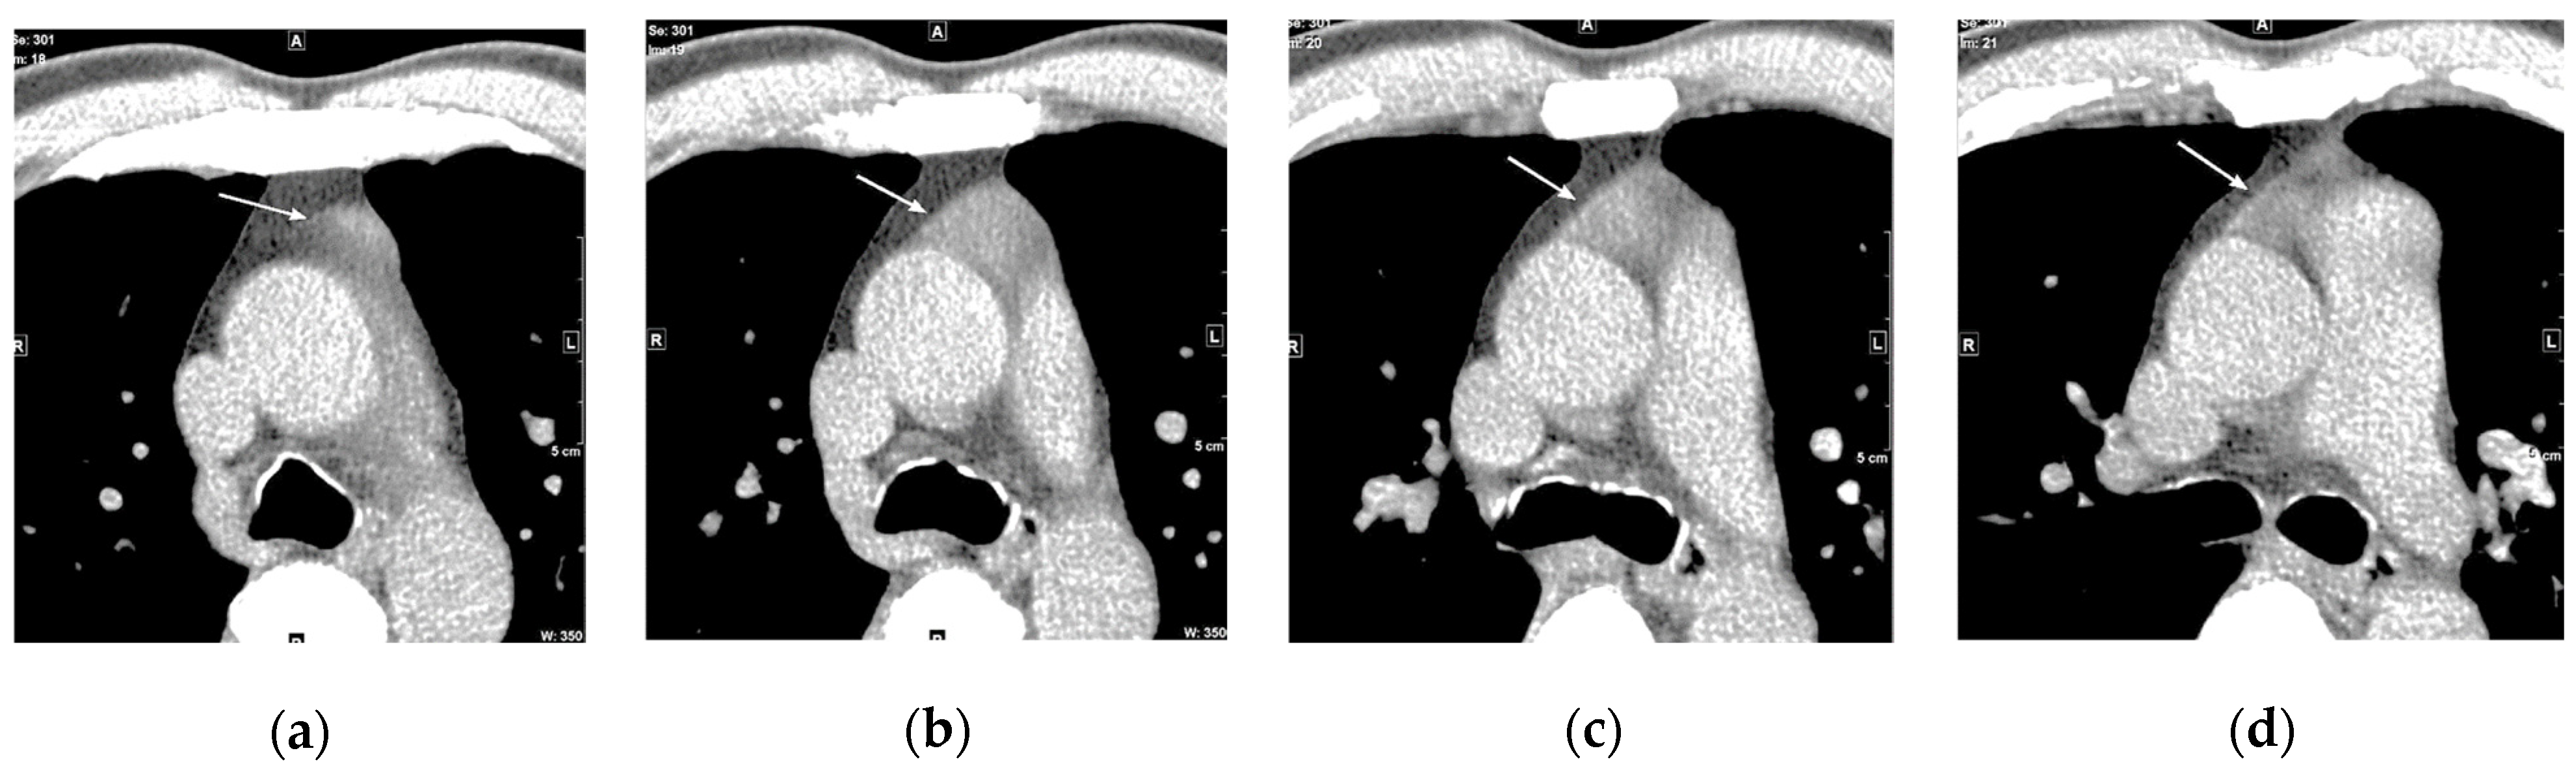

5.1. Neck (Thyroid)

5.2. Breast